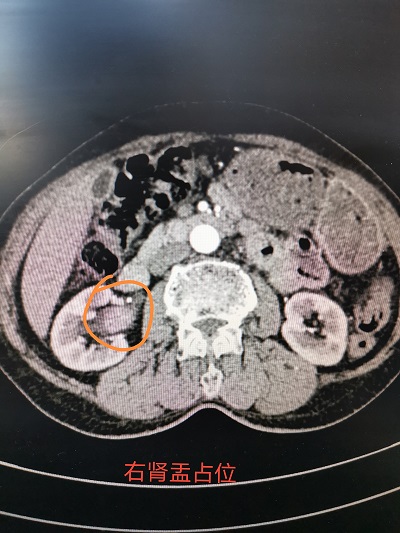

患者女性,74岁,因“间断无痛性肉眼血尿三年”入院,经B超、CT及膀胱镜检查,诊断为右肾盂肿瘤,决定行腹腔镜下肾盂癌根治术。经术前充分准备,在外请专家参与指导下,腹腔镜下行肾盂癌根治术,切除范围包括右侧病变肾脏、右侧输尿管及部分膀胱壁,手术过程顺利,术中出血不多。术后标本病检确定为肾盂尿路上皮癌,目前患者恢复良好。